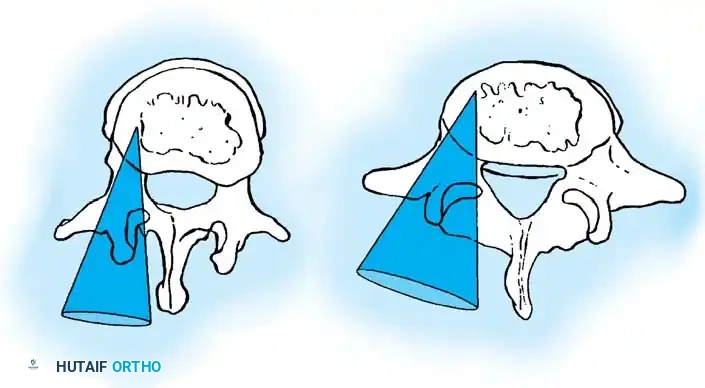

The Moe Technique (Lumbar Spine)

In the lumbar spine, the facet joints are oriented in a more sagittal plane, necessitating a modified approach.

Fig. 38-27: The Moe technique adapted for lumbar facet fusion, addressing the sagittal orientation of the joints.

- Utilize a small osteotome or a needle-nose rongeur to resect the adjoining joint surfaces.

- This creates a distinct rectangular defect within the sagittally oriented joint space.

- Pack this defect forcefully with cancellous bone graft.

- Proceed to decorticate the entire exposed posterior elements (laminae and transverse processes) using Cobb gouges, always directing force away from the spinal canal.